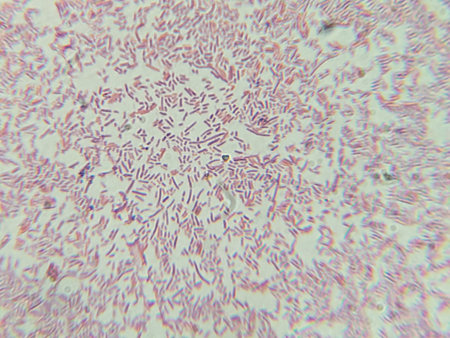

Результат поиска по запросу: "bacillus20anthracis"

Microscopic Section of Lymphoid Tissue Showing Contrasting Follicle Zones

Dense Clumps of Rod-Shaped Bacteria (Bacilli) Under a Microscope